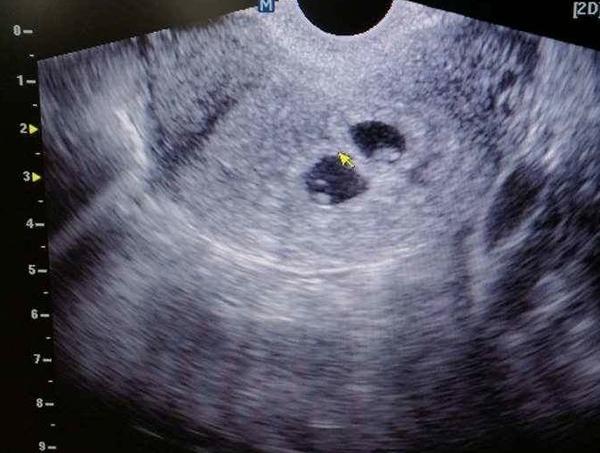

ja som mala na 1. sone 2 plodové vaky, ale akcia srdca bola len v jednom. bola som na konzultáciu u inej dr s lepším sonom asi 4 dni potom, nález rovnaký, síce dvojčatá ale iba 1 živý plod. moja dr ma objednala na kontrolu po 2 týždňoch, bol už iba 1 plod viditeľný. slečna mi už 4,5 roka píli uši